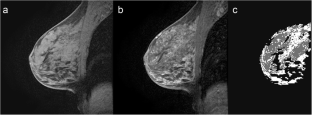

Fig. 3